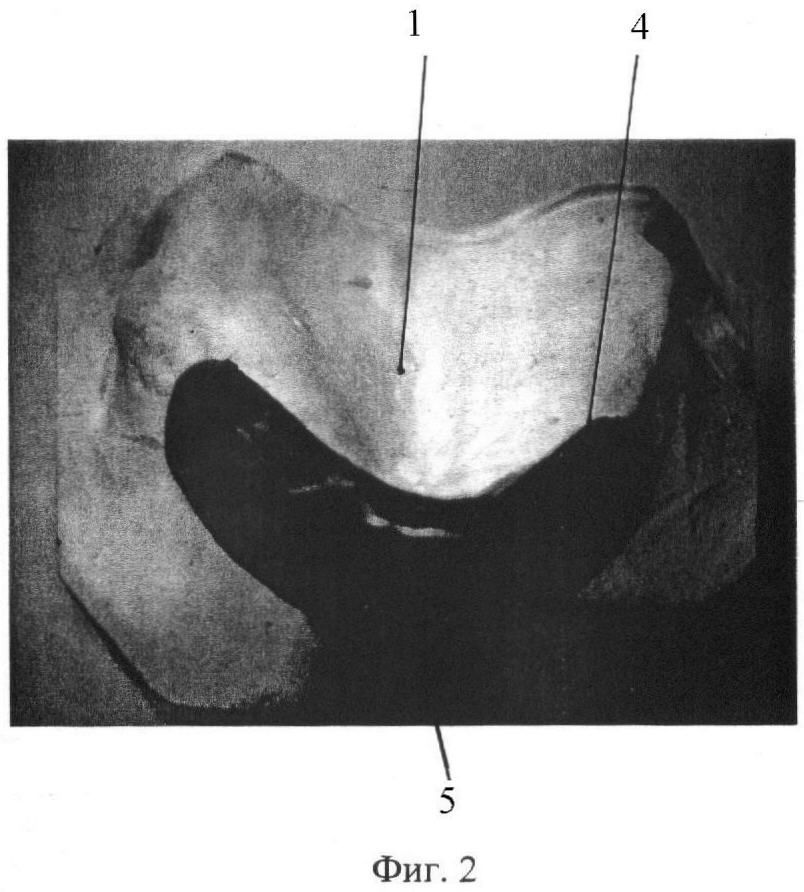

На фиг. 1-3 представлены этапы выполнения способа.

До операции в зуботехнической лаборатории по гипсовой модели 1 челюсти больного (фиг.1), на которой путем гравирования материала в области прикрепления подвижной слизистой оболочки 2 создают высоту 3 ската альвеолярной части, необходимую для фиксации съемного протеза. На полученной модели маркируют границы 4 необходимого кожного трансплантата и в заданных границах 4 формируют восковую модель 5 базиса пластмассового пластиночного протеза (фиг.2), которую традиционным способом заменяют на акриловый пластмассовый пластиночный аппарат. По размерам базиса пластиночного аппарата у больного под местной анестезией забирают кожный тонкий трансплантат, например, с внутренней поверхности плеча и фиксируют швами в раневую поверхность альвеолярной части челюсти, а акриловую пластину 6 укладывают на кожный трансплантат и фиксируют стальными шурупами 7 к компактной пластинке челюсти (фиг.3).

Больной М., история болезни 3312, поступил 08.02.2007 г. на лечение по поводу папилломатоза и выраженной атрофии альвеолярной части переднего отдела верхней челюсти при полном отсутствии зубов. Ввиду сложной клинической картины больному ранее было отказано в ортопедическом лечении. Получена гипсовая модель верхней челюсти, на которой путем гравирования в области прикрепления подвижной слизистой создана высота ската альвеолярной части в переднем отделе, необходимая для фиксации съемного протеза, на модели отмечены границы будущего фиксирующего устройства кожного трансплантата (фиг.1). По отмеченным границам изготовлен пластмассовый пластиночный аппарат (фиг.2). Под местной анестезией удалена папилломатозно измененная слизистая оболочка переднего отдела верхней челюсти, на внутренней поверхности плеча по размерам базиса пластмассового аппарата (фиксирующего устройства) взят тонкий кожный лоскут, который перенесен в дефект слизистой оболочки переднего отдела верхней челюсти и ушит. На кожный перемещенный лоскут помещен пластмассовый акриловый пластиночный аппарат, повторяющий размеры кожного трансплантата, и для достижения плотного прилегания фиксирован стальными шурупами к компактной пластинке верхней челюсти (фиг.3). Послеоперационное течение без осложнений. Назначались антибактериальные препараты в среднетерапевтических дозах, проводилась гипосенсибилизирующая терапия. Больной выписан из клиники на шестые сутки. Через 3 недели амбулаторно удалено устройство, фиксирующее кожный трансплантат, заживление первичным натяжением. Созданы благоприятные анатомические условия для протезирования. Больному наложены полные съемные протезы. На контрольных осмотрах через 3 и 6 месяцев больной жалоб не предъявлял, отмечая хорошие эстетические и функциональные качества протеза.